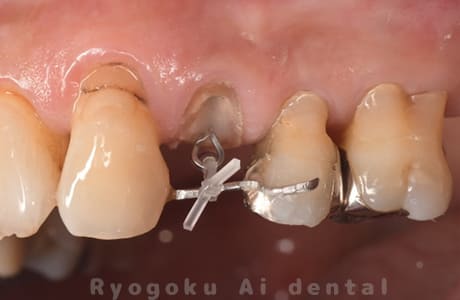

ラバーダムの使用

根管治療では細菌感染には細心の注意を払う必要があります。なぜなら根管内の病巣は細菌感染が原因で悪化するケースがほとんどだからです。

その際にラバーダム(ゴムマスク)という器具を使用します。

ラバーダムは治療をする歯以外をゴムのシートで被うことで治療部位に対しての細菌感染を防ぐ器具です。